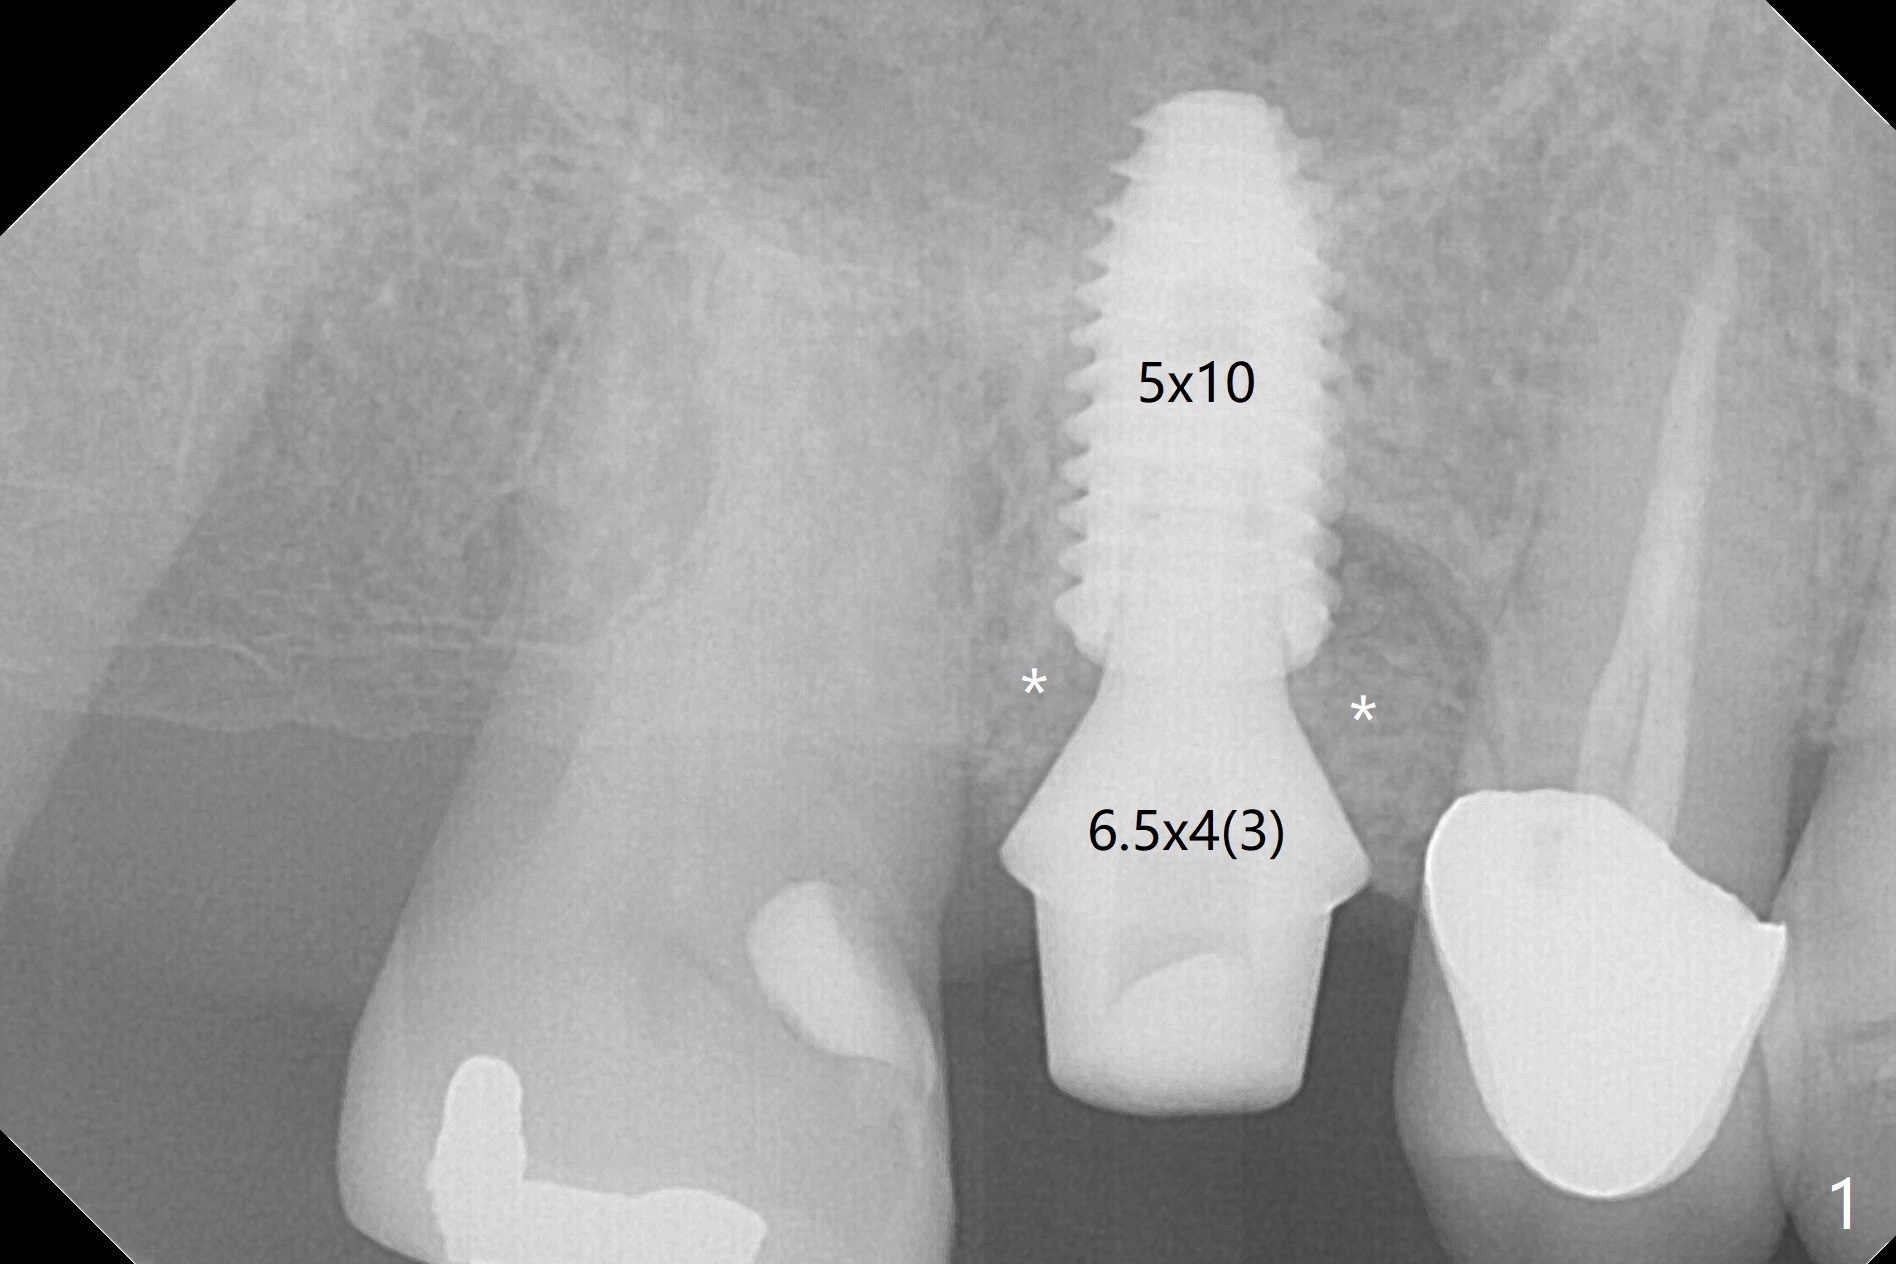

A 5x10 mm implant is placed at #3 according to drill sequence except 4.5x10 mm drill having to be used (plan: underdrilling using 4.0x10 mm as the last one) because of dense bone. Insertion torque is >50 Ncm. Although the implant apparently penetrates the sinus floor (Fig.1), the bottom of the osteotomy is intact before implant placement. In addition, the 12 mm bone trimmer does not touch the septal bone, while 2.2x8.5 mm drill starting to remove bone. In spite of using the largest cementation abutment (6.5 mm), the buccal (Fig.2) and palatal sockets with bone graft (*) are exposed. An immediate provisional (Fig.3 P) is fabricated for remaining socket closure. The buccal gingiva appears to have receded relative to the abutment margin nearly 4 months postop (Fig.4). The mesial crestal bone defect seems to be repairing (Fig.5 (*),6). The abutment later changes to a 5.7x5.5(2) mm one with margin modification buccomesiolingually before impression.